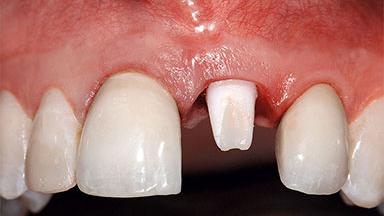

Replacement of a Missing Upper Left Central Incisor: Late Placement of an RC Bone Level Implant, CAD/CAM Zirconia Abutment

A healthy 37-year-old female patient was referred for a consultation on the replacement of missing tooth 21 with an implant-supported restoration. She stated that several years previously the tooth had been traumatically avulsed following a motor vehicle accident. The tooth was replaced with a three-unit fixed partial denture (FPD) immediately afterwards. Over time, she became disillusioned with the FPD and looked for a different option, including orthodontic therapy. She presented still in her orthodontic appliances, with the pontic sectioned free from the FPD but attached to the archwire. Her orthodontist felt that orthodontic treatment had been successfully completed, but nevertheless referred her before removing the appliances in case adjustments were necessary.

Abutment Type CAD/CAM

Prosthesis Type FDP